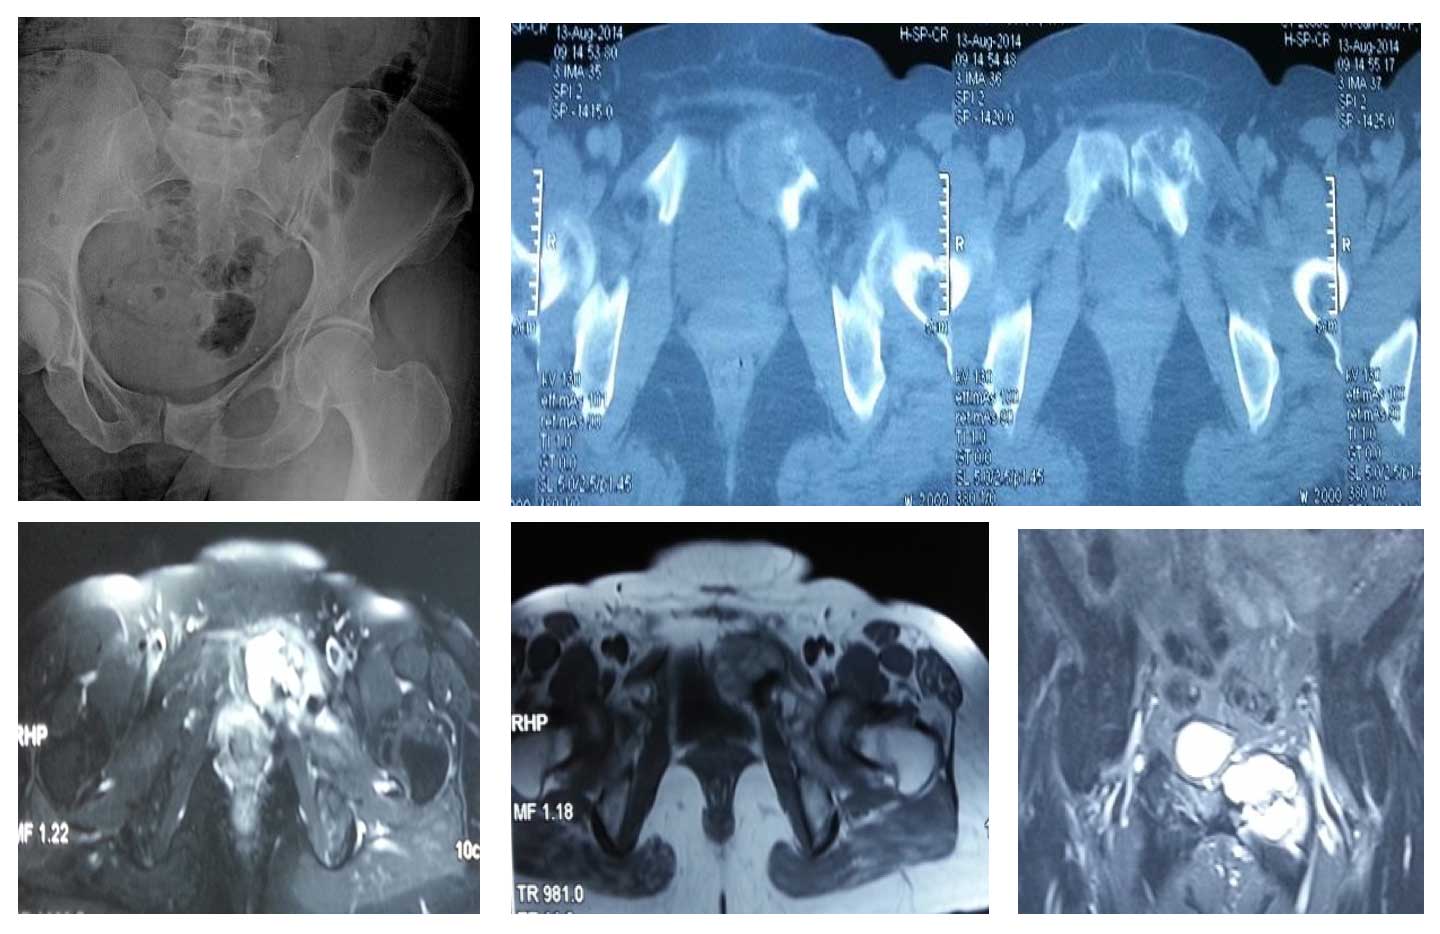

Vaka 16: Pubik Kol Yerleşimli Osteosarkom

Pubik kol yerleşimli osteosarkom, pelvik bölgede nadir görülen bir kemik tümörüdür. Erken tanı ve cerrahi rezeksiyon ile yumuşak doku rekonstrüksiyonu uygulanarak fonksiyonel sonuçlar sağlanabilir.

43 yaş kadın hasta

Kasıkta ağrı ve şişlik şikayeti

Sol süperior pubik kol yerleşimli osteosarkom

Taramalarda metastaz yok

Ameliyat Öncesi: Röntgen’de düzensizlik, tomografi’de kemik harabiyeti, MR’da yumuşak doku komponenti görülmekte.